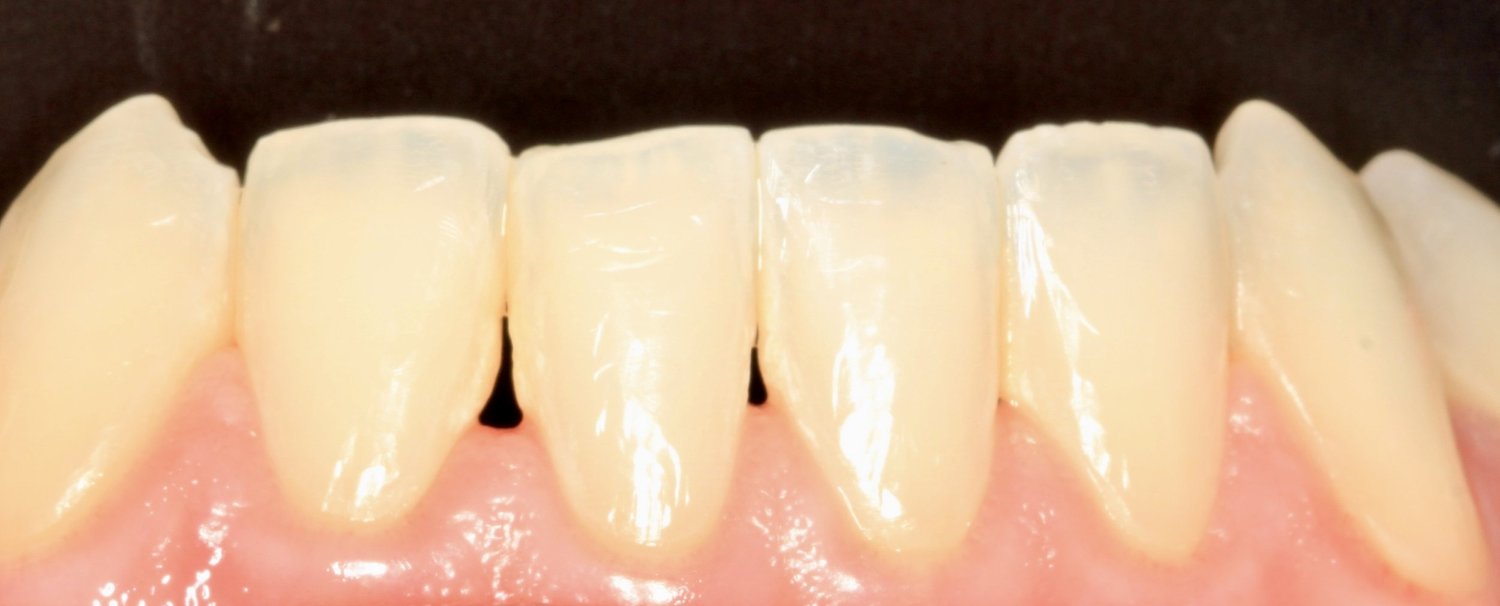

Before

After